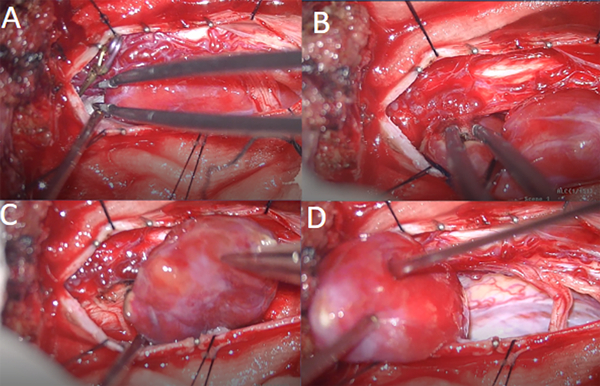

Fig 4. Caso 1. Imágenes intraoperatorias. Clipado transitorio de vasos aferentes (A). Coagulación y sección de vena de drenaje (B). Remoción en bloque (C y D).

Posicionamos al paciente en decúbito prono con soporte dorso lumbar. Se utilizó cabezal de Mayfield para fijar la cabeza. Se realizó incisión lineal desde C2 a C5. Se disecó tejido hipodérmico hasta ligamento vertebral posterior; se abrió la fascia muscular hasta exponer las apófisis espinosas y las láminas. Se procedió a realizar laminectomía C3-C5 y flavectomía C2-C6. La duramadre fue abierta en forma lineal. Se realizó monitoreo neurofisiológico con onda D. Se visualizó lesión voluminosa que desplazaba raíces y cordón medular a derecha de color gris-rosada, vascularizada que impresionaba nacer de raíz sensitiva C4 izquierda. Se colocaron en ambas aferencias arteriales en el polo superior, clips transitorios por 5 minutos sin cambios neurofisiológicos, continuando con la sección de ambas aferentes. Se luxó la lesión que quedó pendiente de vena arrosariada en cara posterior de la médula, la cual se coaguló y seccionó con remoción de la lesión en bloque.

En cuanto a la técnica quirúrgica, la resección de hemangioblastomas medulares presenta algunas similitudes con la cirugía de las malformaciones arterio-venosas. Se recomienda una exposición amplia en lesiones muy vascularizadas. Es por ello que consideramos habitualmente en este tipo de lesiones la realización de laminectomía completa por sobre hemilaminectomía. El procedimiento conlleva una devascularizacion tumoral y coagulación de arterias aferentes con eventual clipado transitorio de las mismas y, por último, coagulación y sección de vena de drenaje con resección en bloque de la lesión para evitar sangrado intraoperatorio .